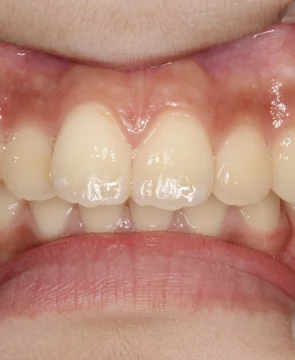

2026/02/24上の前歯が捻じれていることが気になる7歳女児の矯正症例紹介 患者様は上の前歯が捻じれていることを気にされており、矯正検査後叢生Ⅰ級と診断いたしました。 治療前後の比較 矯正術前:正面 矯正術後:正面 矯正術前:右側 矯正術後:右側 矯正術前:左側 矯正術後:左側 矯正術前:上顎 矯正術後:上顎 矯正術前:下顎 矯正術後:下顎 矯正術前:前歯部あおり 矯正術後:前歯部あおり 矯正術前:オーバージェット 矯正術後:オーバージェット 主訴 上の前歯が捻じれていることが気になる 治療期間 ・マウスピース矯正:6カ月 治療費用 660,000円…